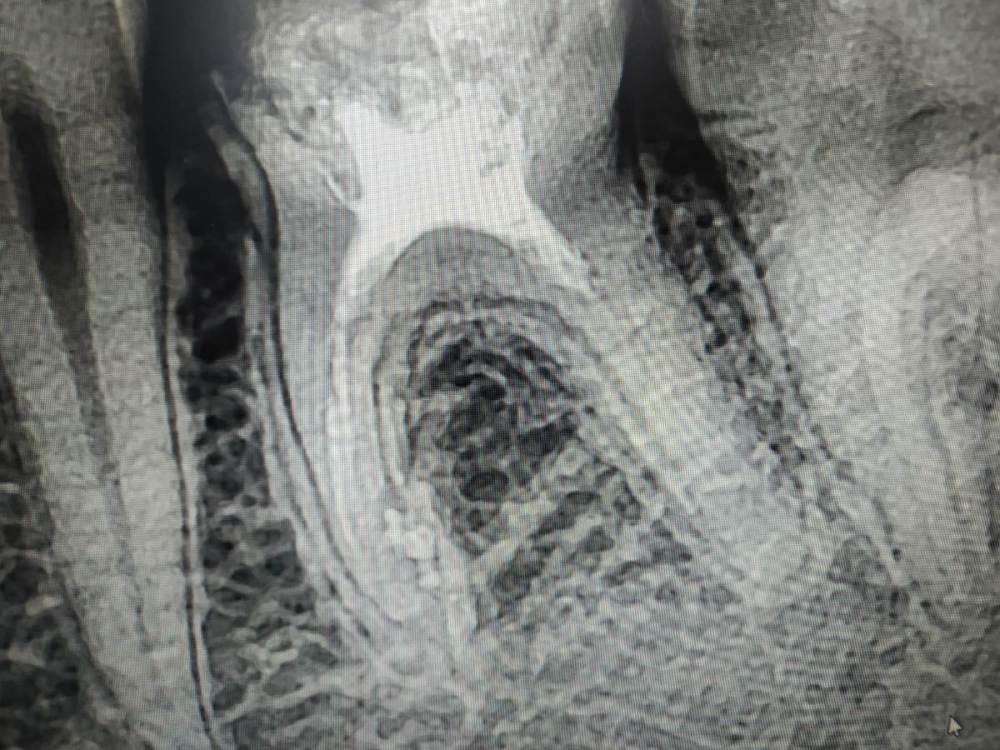

это да, но бывает, это устье раздваивается далеко не в устьевой части корня,а глубоко в средней , например как тут, хз как туда попасть

post-56770-0-48666200-1582799105_thumb.jpg

мое мнение(человека без микро), в этом случае нужно просто работать в ванночке из ГХ, он растворяет пульпу, а вовремя пломбировки это ответвление  заполнится силером.

Ничего не запомлнится,к сожалению, если не обработать механически.Измеряете на снимке расстояние до разветвления-стопер на файле 08 ставите так же и гнете кончик файла язычно,либо вестибулярного. Потихоньку тыкаемся и поворачивает,тыкаемся и поворачивает файл(подобно байпасу)нашли один канал-берете следующий 08,не вытаскивая первый и повторяет действия